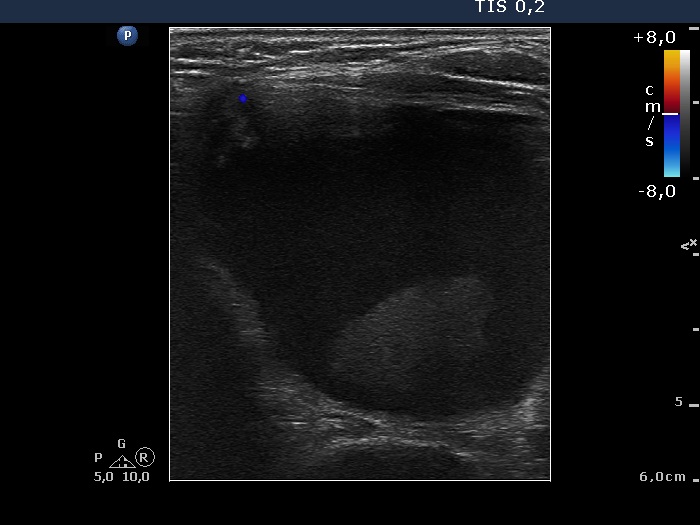

Differentiation of discrete lesions - case 230 (ultrasonographic picture 5)

Left lobe, horizontal scan, color Doppler mode. The lesion is avascular on Doppler mode.